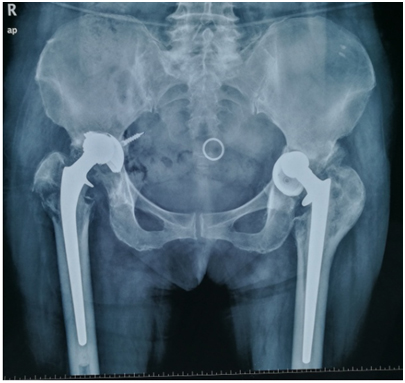

最近,关节与骨肿瘤外科完成一例高难度双侧髋关节翻修手术。患者74岁高龄,翻修手术难度大、出血多,术后易出现感染、血栓等并发症,所以对手术团队要求很高,这例手术的成功完成标志着我院关节外科的翻修技术达到了一个新的层次。 韩老太太,今年74岁。2005年因为双侧股骨头坏死在我院行双侧髋关节置换术。术后恢复快,3天能够下地行走,随后在家中就可以正常活动。2015年时患者开始出现左侧髋关节痛,随后不久出现右侧髋关节痛。2016年下半年开始疼痛逐渐加重,不能行走,需要借助轮椅。2017年初甚至休息卧床期间都出现疼痛症状。家人带患者来我院关节外科尹宗生主任门诊求治,检查发现患者双侧髋关节均已出现松动,由于疼痛已经严重影响生活质量,所以必须选择翻修手术治疗。术前科室对手术进行了详细的计划,利用先进的3D打印技术重建关节骨骼模型,术前对髋臼的骨缺损进行了预判,同时对术中可能出现的问题进行了充分的准备。